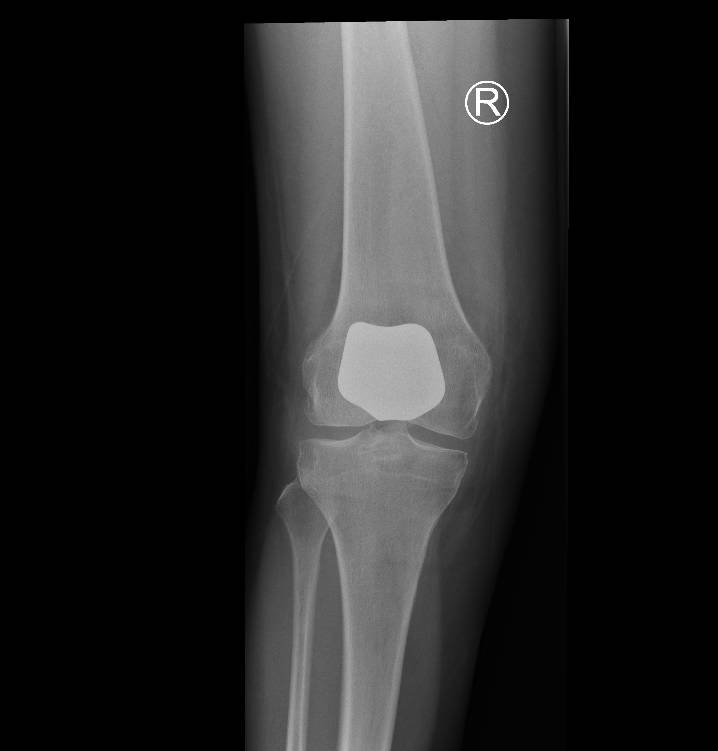

Through a minimally invasive midline incision the patellofemoral joint of the knee is replaced. This consists of a metal femoral component and a polyethelene (plastic) patella button. The unaffected medial and lateral parts of the joint are preserved along with the cruciate ligaments so the knee will feel ‘more normal’ thus providing improved functional results following surgery.